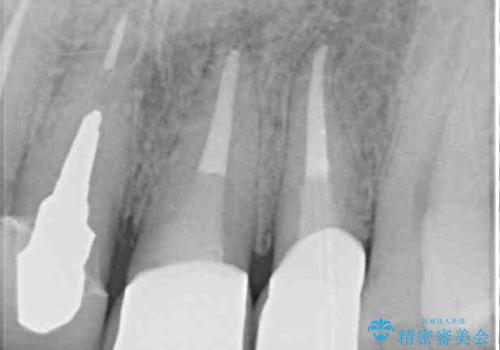

根管治療を実施した後、オールセラミッククラウンに補綴することとしました。

前歯のセラミッククラウンを装着したばかりであったので、根管治療のためにクラウンを壊さなければならないことを残念に思っていらっしゃいました。

しかし、根管治療後はすぐに痛みがひき、治療を受けられて良かったとのことでした。